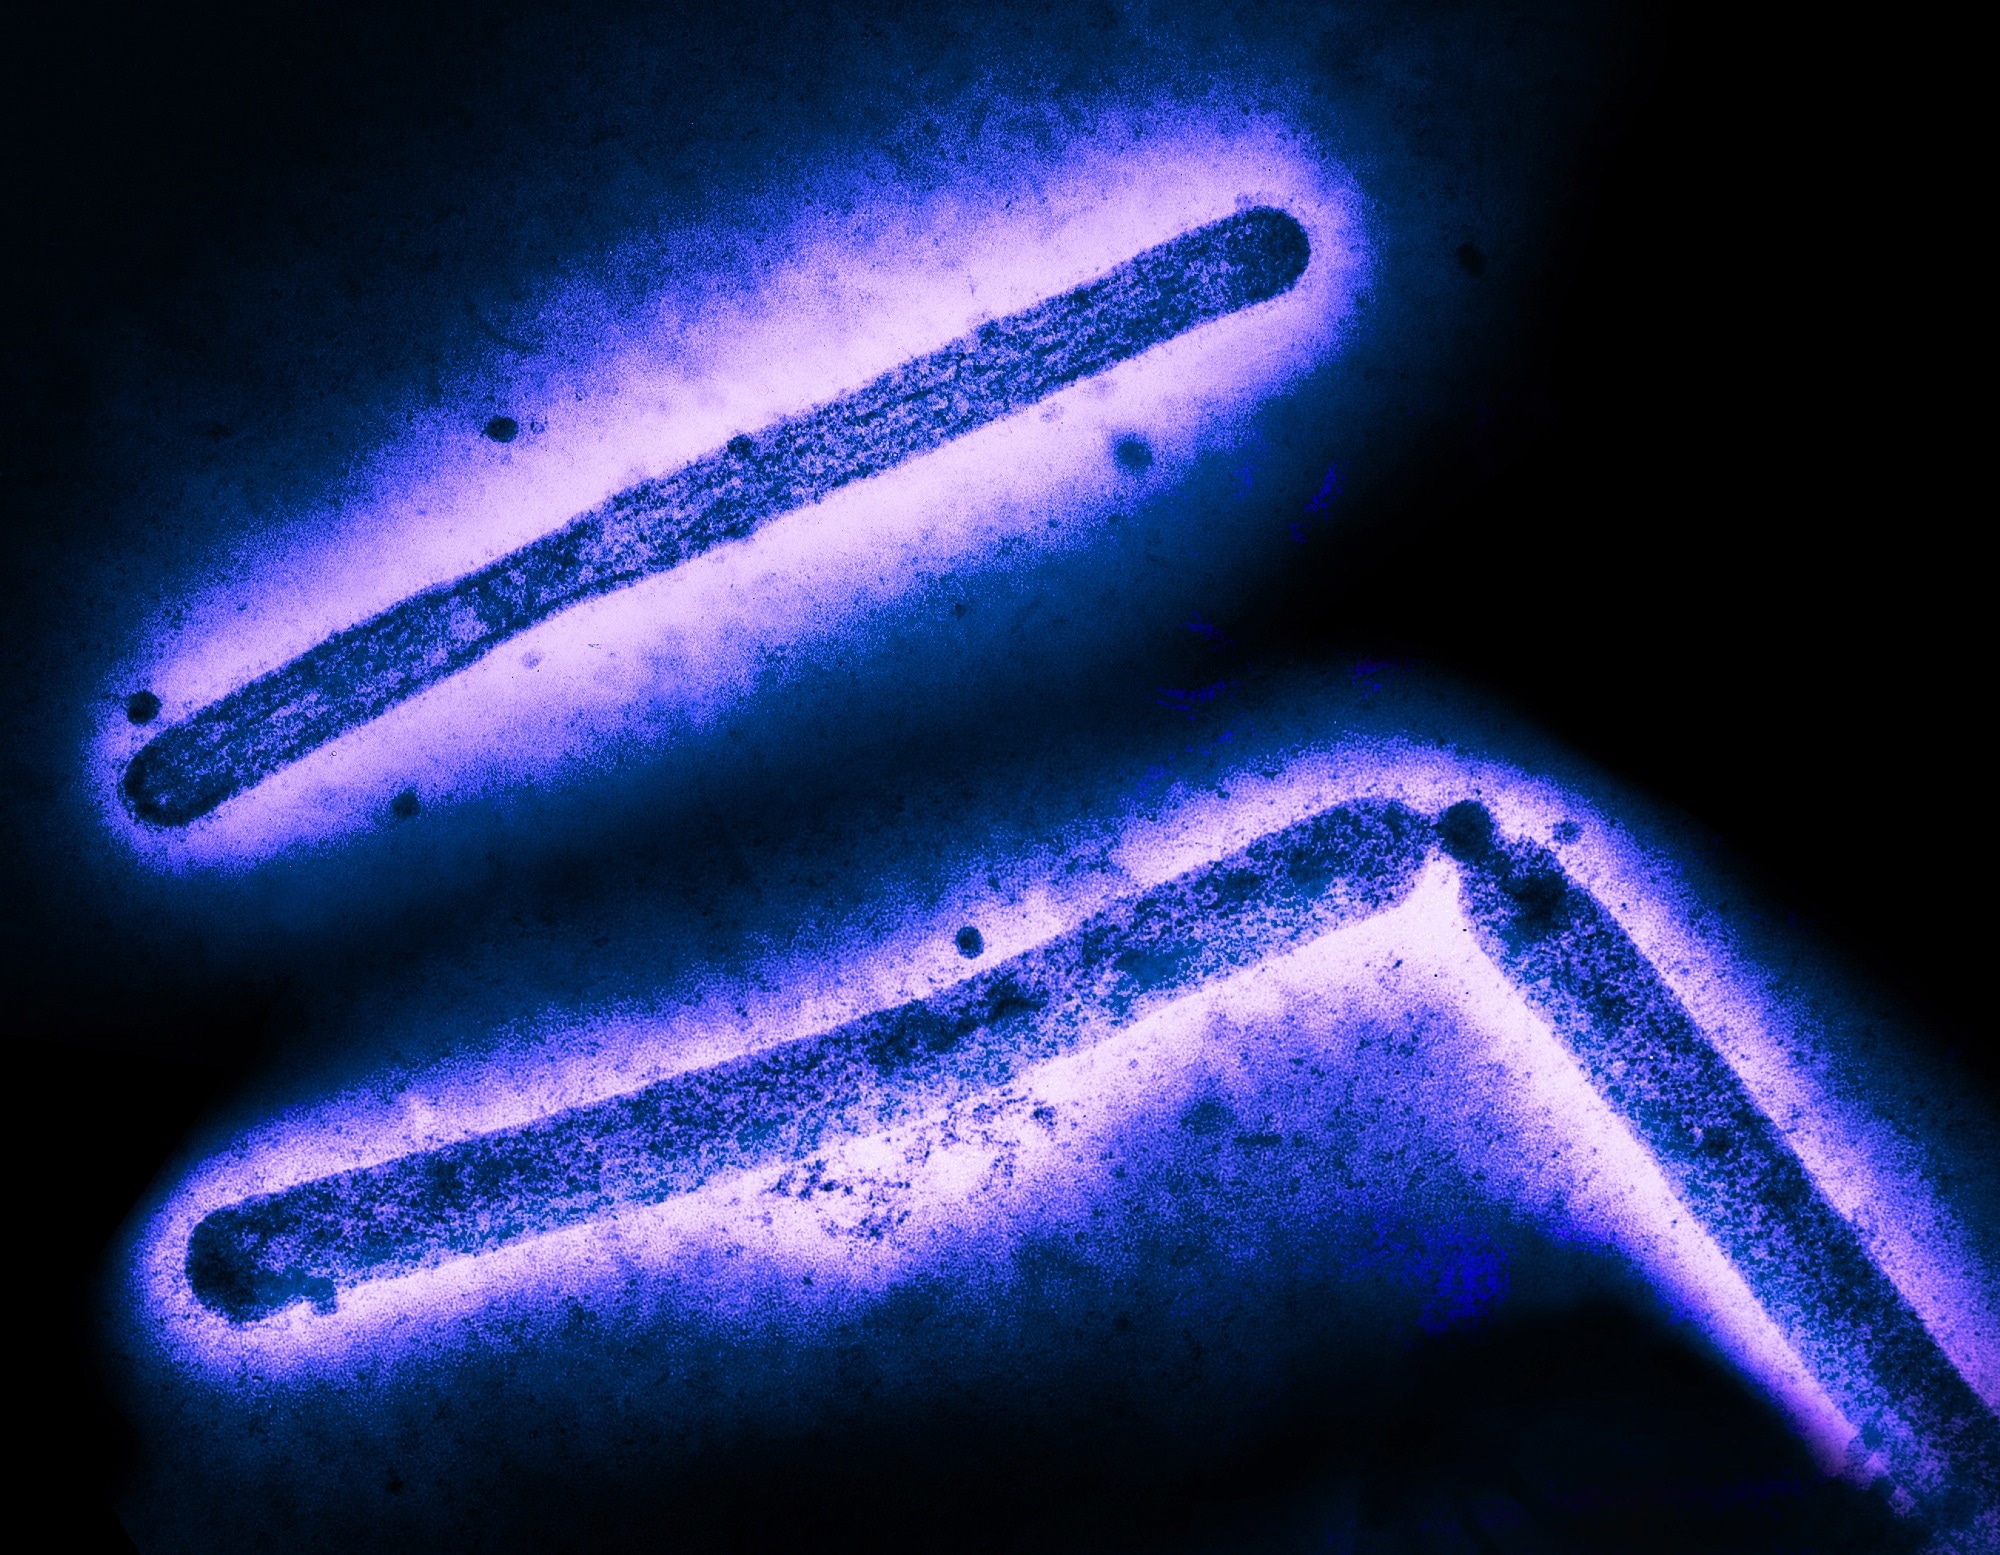

Study: Rapid evolution of A(H5N1) influenza viruses after intercontinental spread to North America. Image Credit: CDC and NIAIDStudy: Rapid evolution of A(H5N1) influenza viruses after intercontinental spread to North America. Image Credit: CDC and NIAID